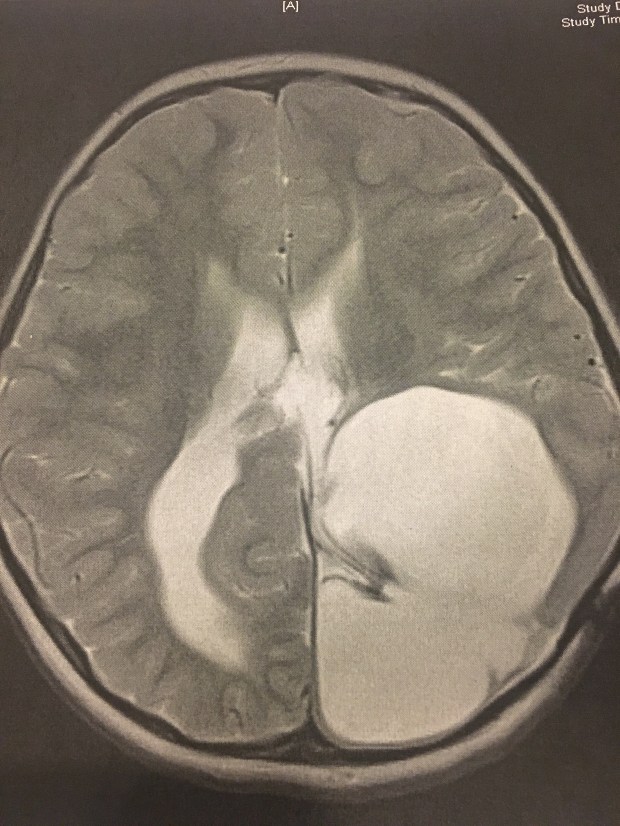

I don’t know that I’ve shared a picture of Harper’s brain before, so I have one to share tonight:

All of that white space in this image shouldn’t be there. The thinner white strip on the left side of the picture is fluid accumulation in an enlarged ventricle. And that huge white blob on the right side? That’s a cyst and dead brain tissue. All of the white in the image is taking the place of what should be functioning brain tissue… and amazingly enough, this is an incredible improvement from what this image showed five years ago.

What does that mean? It means this girl really shouldn’t be able to do much of what she does. She walks. She talks. She laughs. She sings and dances and plays and learns. She can see and she can hear and every day with her is a day that God is working mightily. It is a miracle.There are moments that I get overwhelmed or I feel sad that she struggles in some way. There are times that I think it isn’t fair or I get scared for what the future will hold. Today I felt all of those things (and more) at one point. But tonight as I look away from that MRI picture and look instead at the bigger picture, I am reminded once again that we serve a God who sees the whole picture. He sees and He knows and He has plans far beyond what I can dream, and in the meantime He has given me so very much to be thankful for. ❤️